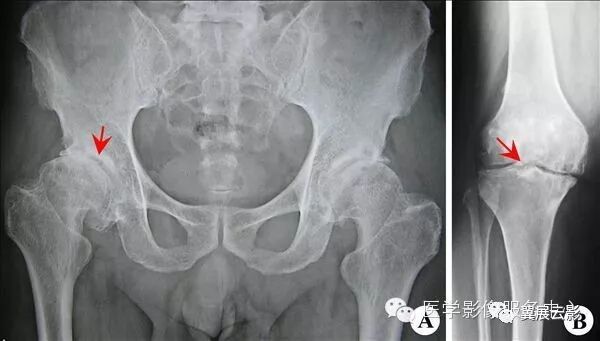

【影像表现】:X线平片(A、B)示骨小梁减少、变细,骨密度减低,骨皮质变薄。【影像诊断】:骨质疏松。

【影像表现】:X线侧位片示股骨远端一带蒂背关节生长的骨性突起(↑),其骨皮质、髓腔分别与股骨相应部分相连,顶端软骨帽钙化。【影像诊断】:股骨远端单发性骨软骨瘤(带蒂型)。

【影像表现】:MRI平扫T1WI(A)、T2WI(B)示 腰1椎体呈楔形改变(↑),胸12~腰1椎间盘后突。【影像诊断】:椎体压缩性骨折。